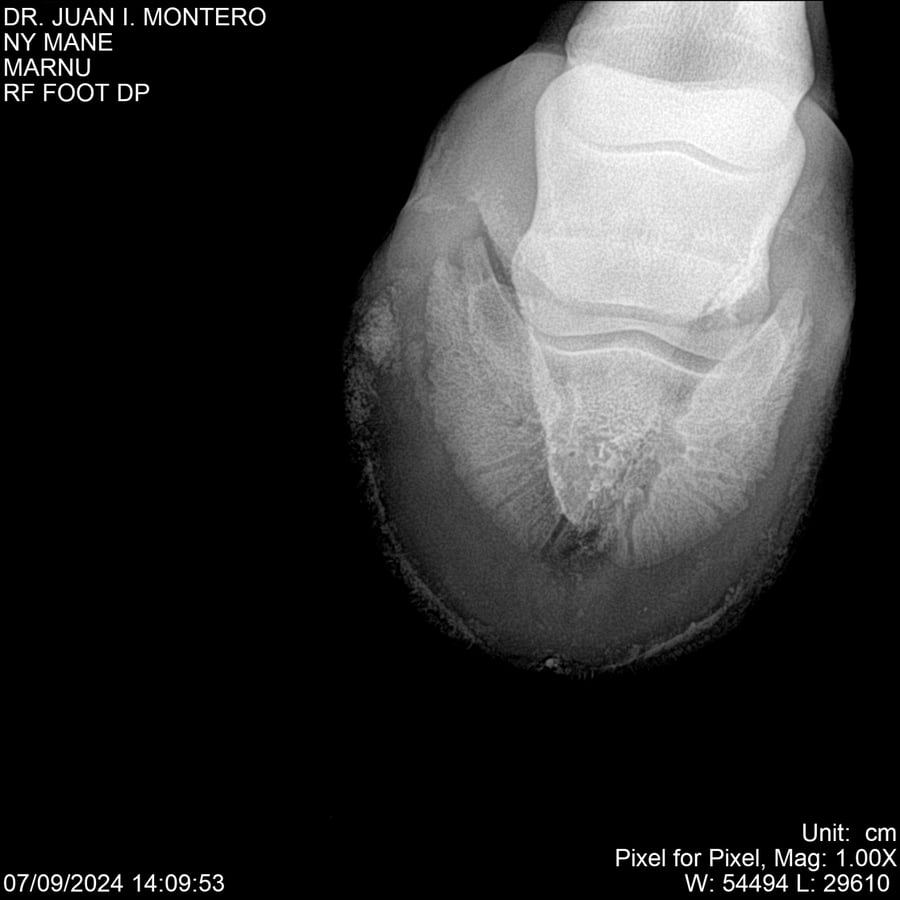

LOTE 20, NY MANE Lote Anterior Volver al remate Lote Siguiente Ficha Contacto Montevideo - Ficha del Lote Identificador: #282520 Categoría: Yeguarizos 76 Visualizaciones ClicData Contacto Empresa: Abelenda N. R., Walter Hugo Nombre*: Teléfono* : E-mail* : Mensaje Enviar Registrese gratis Este contenido Exclusivo está disponible sólo para usuarios registrados Ingresar